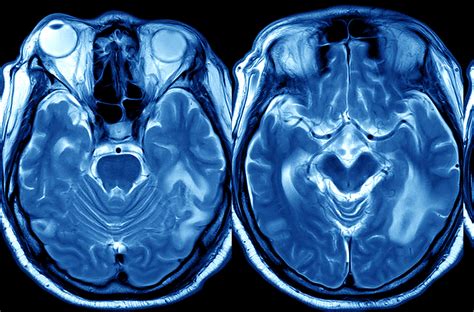

La TC e la RM possono mostrare:

- Infarti multipli bilaterali nell'emisfero dominante e nelle strutture limbiche.

- Ictus lacunari multipli.

- Lesioni periventricolari della sostanza bianca.

- Nella demenza di Binswanger, leucoencefalopatia del centro semiovale, spesso con lacune multiple nelle strutture profonde della sostanza grigia.

- Nel CADASIL e CARASIL, iperintensità diffusa della sostanza bianca con lesioni ischemiche sottocorticali, compreso il lobo temporale anteriore.

- Nell'angiopatia cerebrale da amiloide, emorragia lobare, microemorragia corticale multipla o siderosi superficiale.